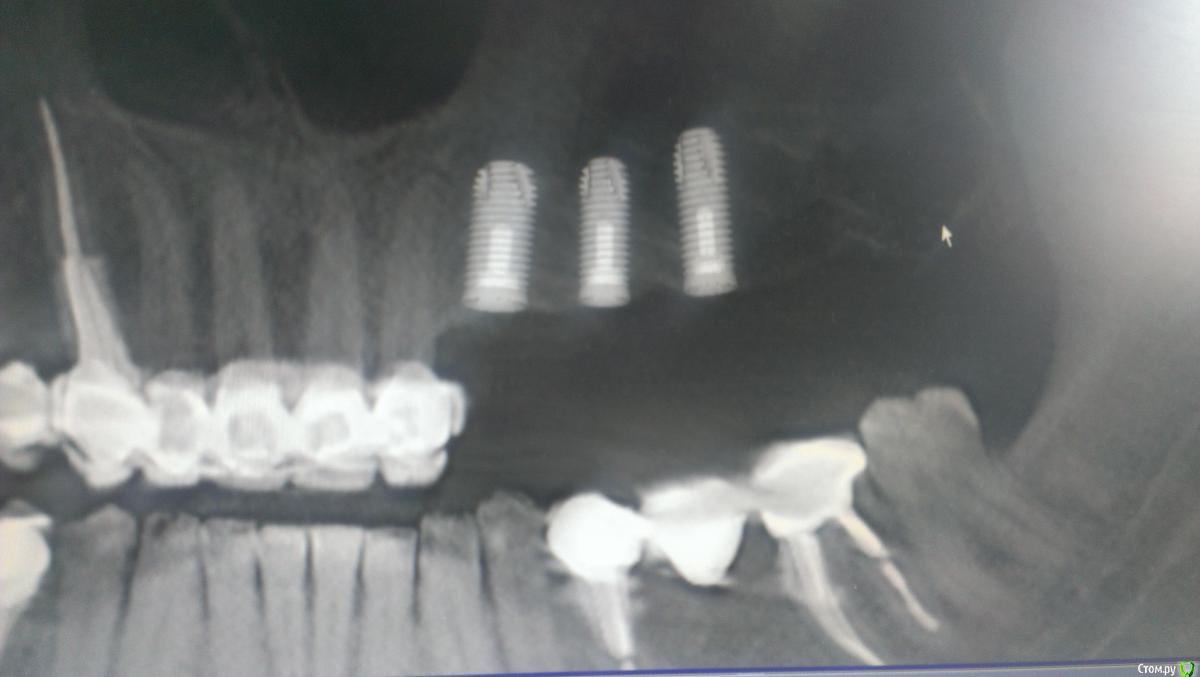

AlexFox Опубликовано 13 июля, 2016 Поделиться Опубликовано 13 июля, 2016 Доброго времени суток,коллеги.Огромная просьба к имплантологам поделиться своим мнением по-поводу клинического случая.Пациенту 45 лет,жалобы на отсутствие жевательной группы зубов во втором сегменте.Для постановки имплантов требуется синуслифтинг.Меня настораживает малый объем имеющейся костной ткани при большом объеме поднятия дна.Плюс слизистой на кт я вообще не вижу.Хотелось бы узнать ваше мнение об этом. Ссылка на комментарий

BugDan Опубликовано 14 июля, 2016 Поделиться Опубликовано 14 июля, 2016 (изменено) Я бы сделал синус с ауто-ксено 1:1 по причине чистой кортикалки в области моляров.Ставить ли импланты сразу или нет зависит от макродизайна имплантатов котрыми вы планируете пользоваться и опыта в первую очередь.На картинках планирования 23 стоит далековато от 22 , винт 5 стоит чуть медиальнее чем надо, а 6 сильно медиальнее чем нужно. Для страховки просмотрите латеральную стенку синуса на предмет артерии. Изменено 14 июля, 2016 пользователем BugDan Ссылка на комментарий

Astronaft Опубликовано 14 июля, 2016 Поделиться Опубликовано 14 июля, 2016 23 занчительно мезиальнее надо.Я бы ограничился 3 винтами задесь, поставив 25 под углом, что бы вышел на 26. 1 Ссылка на комментарий